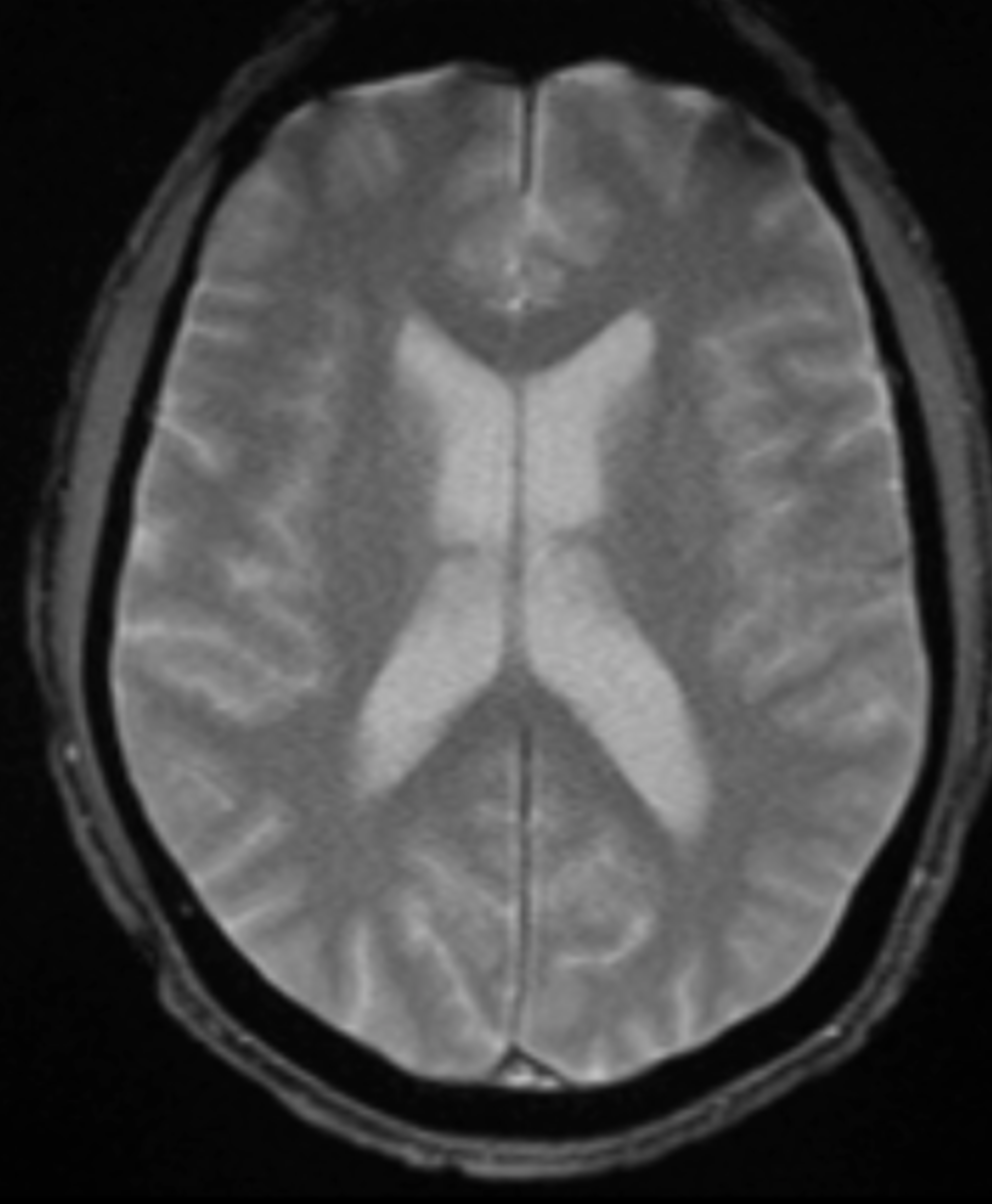

Quelle est la séquence de cet IRM ?

T2 étoile